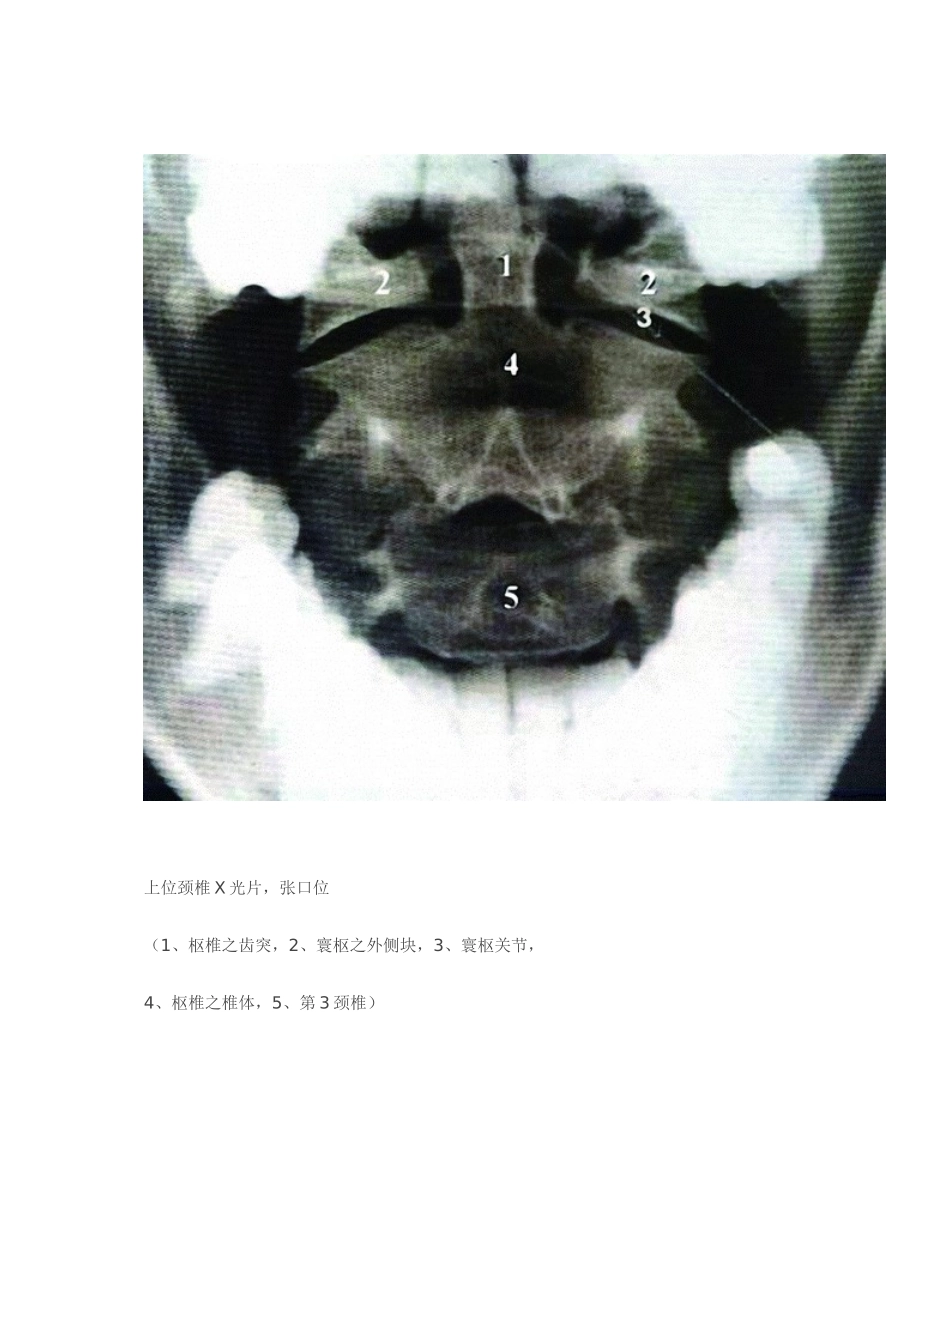

颈椎正位X线片(1、钩椎关节,2、第三颈椎椎体,3、棘突,4、横突)(本例4、5钩椎关节不对称)下位颈椎与上位胸椎X光片(1、第6颈椎之椎体,2、气管阴影之缘,3、椎体4、横突,5、肋骨头,6、肋骨颈,7、肋骨结节,8、肋骨体,9、肋骨头,10、肋骨颈,11、肋骨结节)上位颈椎X光片,张口位(1、枢椎之齿突,2、寰枢之外侧块,3、寰枢关节,4、枢椎之椎体,5、第3颈椎)颈前侧位X线片,脊柱颈曲清晰可见(1、舌的咽部,2、会厌软骨,3、舌骨体,4、甲状软骨正进行钙化,5、寰椎前结节,6、枢椎棘突,7、软腭,8、特征性颈椎椎体,9、椎间盘,10、关节突关节,11、气管内空气)颈椎标准侧位像生理曲度(A、X线片测量法,图中示正常椎曲;B、图示下颌角A平C2下缘,示第1椎棘突基底部向下至第7颈椎后下缘连线,其中点连线经过C4、5间为正常椎曲)腰椎弓顶距离及前突指数(Seze测量法)(A、X线片测量法;B、弓顶距离测量图示12胸椎后下缘向第1骶椎后上角连线正常a线为1.8~2.2cm,前突指数b线正常2.5cm以内。腰椎斜位像(椎弓关节及椎弓在斜位像上近似一狗的外形,1、耳为上关节突,2、其嘴相当于横突,3、颈为峡部,4、前腿为下关节突,5、体为椎弓,6、体之后部为椎弓及对侧之上关节突与下关节突,7、为椎体)腰椎骶化不全椎间盘病变CT片:中央型腰椎间盘突出椎间盘病变CT片:左侧椎间盘突出及钙化椎间盘病变CT片:椎间盘突出,黄韧带肥厚椎间盘病变CT片:右侧椎间盘突出,侧隐窝增大,神经根完全受压手法复位后突出物基本回纳。左侧椎间孔已清楚,26.4X7.0mm硬膜囊已无受压,囊外脂肪层亦清楚正常腰椎矢状位MRT1WI表现和正常腰椎矢状位MRT2WI表现